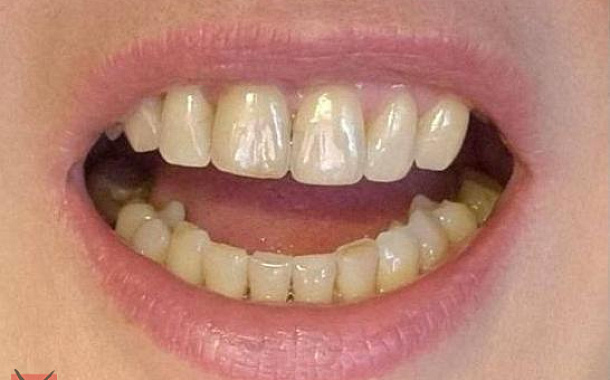

- Точное планирование: Детальные 3D-модели позволяют нашим специалистам тщательно спланировать каждый этап лечения, учитывая все анатомические особенности пациента.

- Визуализация результатов: Пациенты могут увидеть предполагаемый результат лечения еще до его начала, что помогает в принятии информированных решений.

- Максимально точные и эстетичные ортопедические конструкции